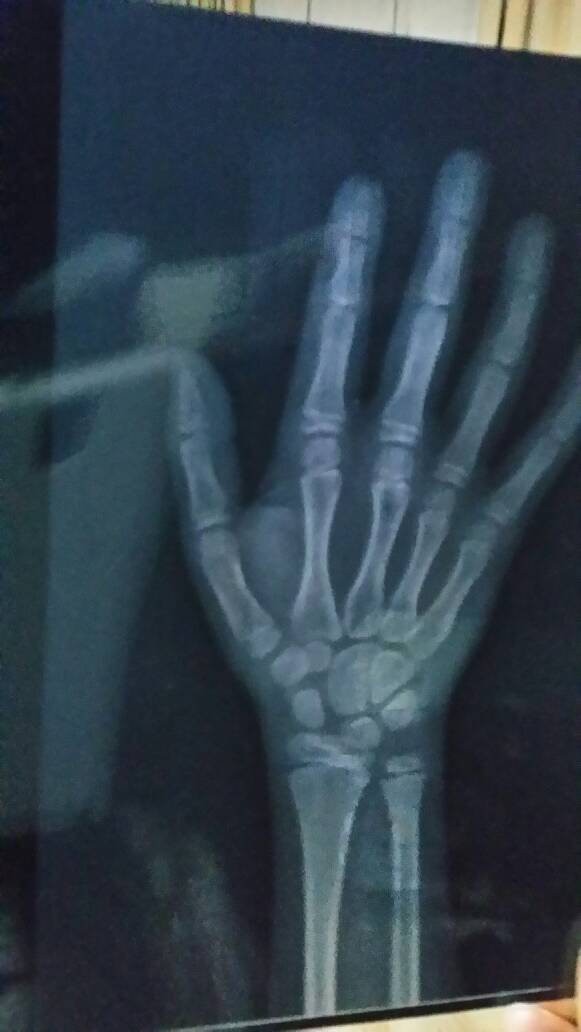

我家小孩身体好,很少生病,可就是长得慢,到医院查骨龄是9岁,医生说要打生长激素针,激素针有副作用吗?不打可以吗?是不是以后长不高?

病情分析: 你好,这种情况的话,额外的补充生长激素利于孩子的生长,不然会比较矮的。而且现在是孩子生长比较快的时期,要尽快的按照医生的建议来打,一旦错过时间之后,就没办法了,就会很矮也没有其他的办法。 指导意见: 1、建议你按照医生的建议来。 2、尽快给孩子用药吧。 3、生长激素的量需要结合孩子检测出...来的量来打,不能过量。 4、如果按照正确的量来打的话,不会有什么副作用